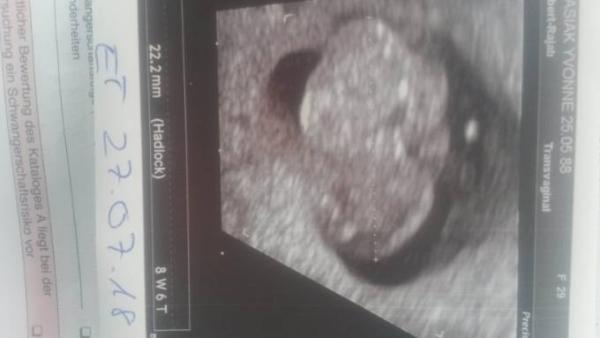

Hab heute auch Termin gehabt zum krümelchen gucken und diesmal konnte es sich auch nicht mehr verstecken. Misst jetzt 2,2 cm... soweit alles gut. Mein Mann freut sich jetzt auch, hat das Bildchen gleich als Status bei WhatsApp rein ...und bin noch vordatiert worden auf 27.7.